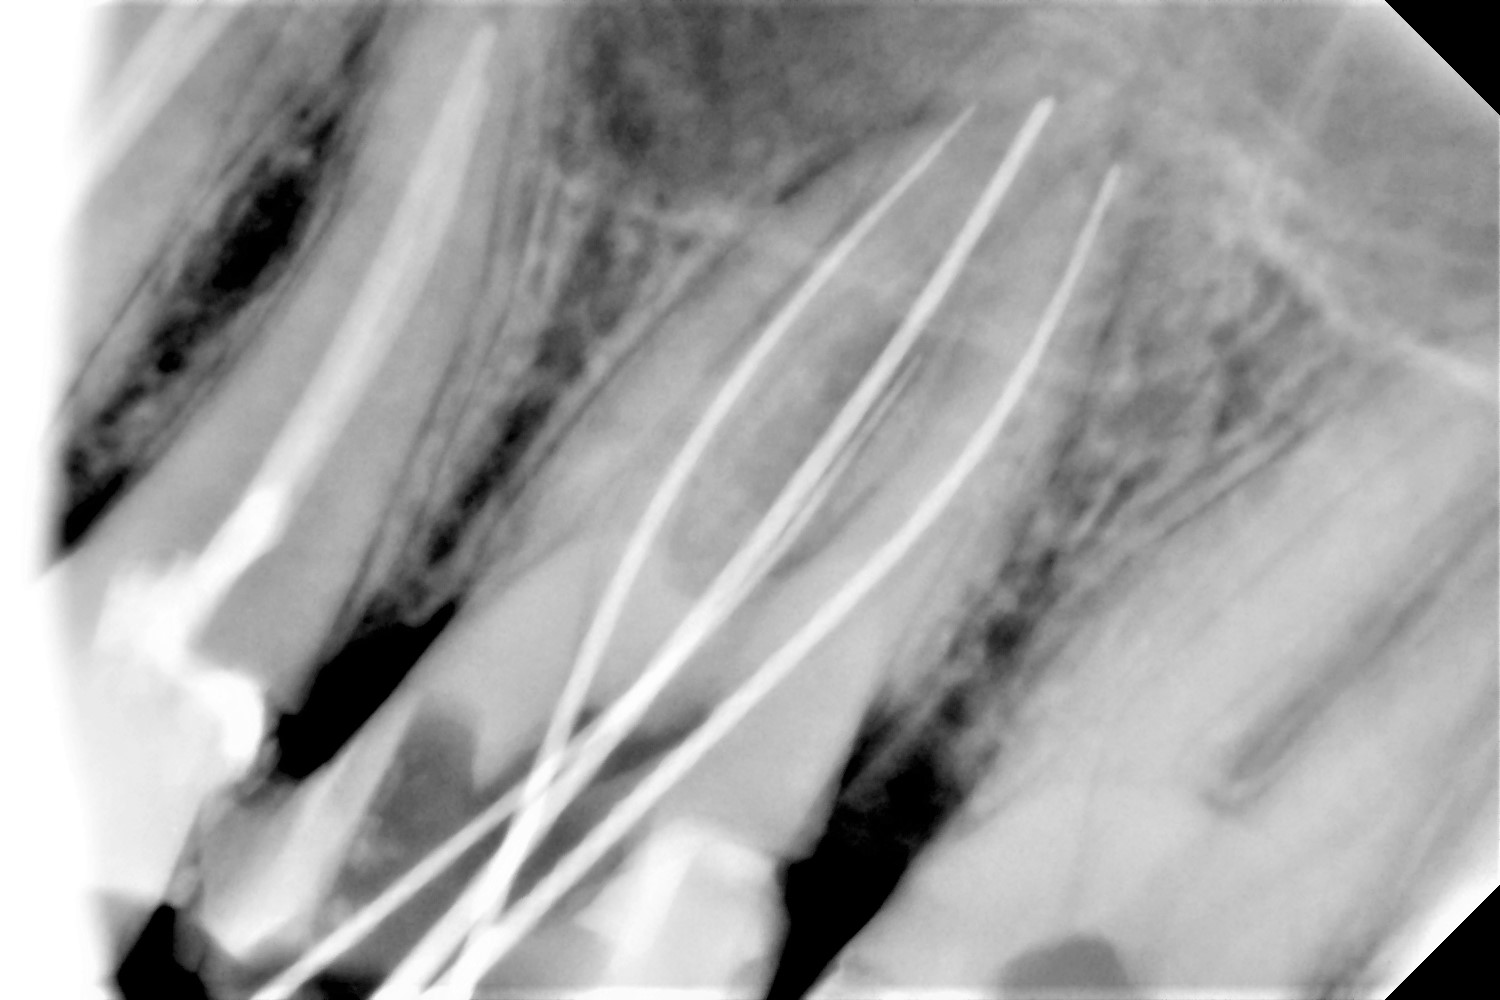

Η ενδοδοντική θεραπεία,απονεύρωση,είναι απολύτως αναγκαία όταν η τερηδόνα έχει προχωρήσει σε τέτοιο βαθμό,ώστε να προσβάλλει τον πυρήνα του δοντιού,δηλαδή τον πολφό.Όταν υποστεί βλάβη ο πολφός και αρχίσει να νεκρώνεται,δημιουργούνται φλεγμονές και αποστήματα στο ακρορρίζιο που προκαλούν έντονο πόνο και πρήξιμο στον ασθενή.Για το λόγο αυτό η έγκαιρη παρέμβαση του οδοντιάτρου είναι απαραίτητη,όχι μόνο για την ανακούφιση των συμπτωμάτων,αλλά κυρίως για να σωθεί το δόντι.